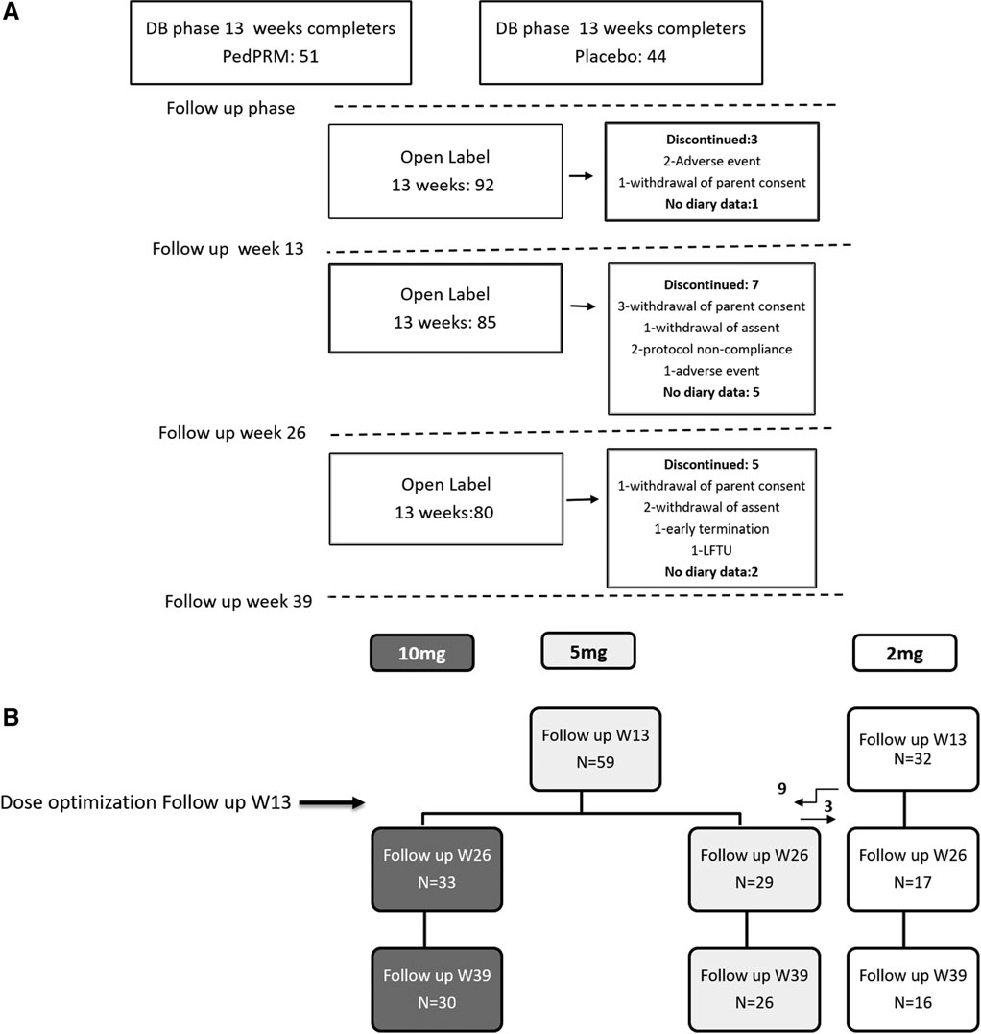

Study enrollment and participant flow for a long-term follow-up trial of prolonged-release melatonin (PedPRM) in children and adolescents with autism spectrum disorder and insomnia. The diagram tracks participants through screening, treatment phases, and follow-up periods.

Long-Term Efficacy and Safety of Pediatric Prolonged-Release Melatonin for Insomnia in Children …